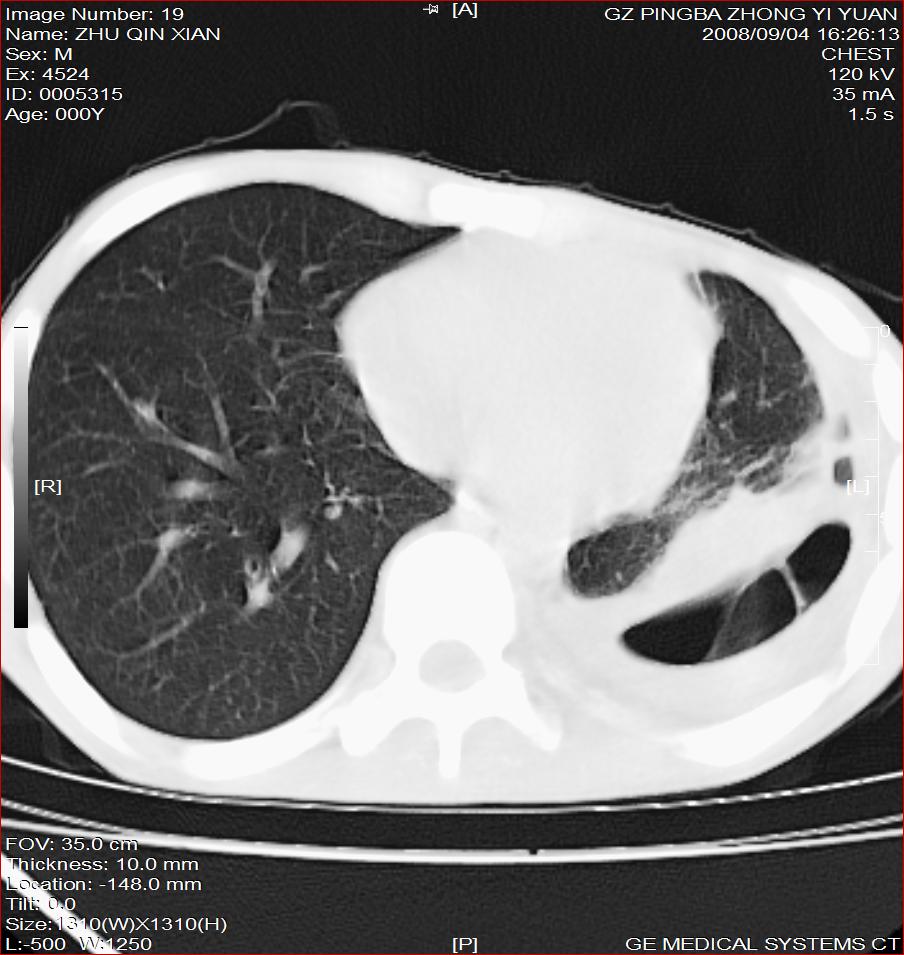

以下是引用随光逐影在2008-9-4 20:05:00的发言:[br]1)考虑两肺结核。2)左侧胸膜炎(胸膜肥厚、粘连,胸腔积液)。3)左侧局限性气胸。

以下是引用子十在2008-9-4 19:34:00的发言:[br]左上肺结核并空洞及双肺播散。节段性肺不张、胸腔积液、胸膜肥厚粘连。[br]